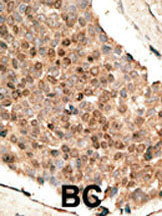

Supportive validation

- Submitted by

- Abcepta (provider)

- Main image

- Experimental details

- "Formalin-fixed and paraffin-embedded human cancer tissue reacted with the primary antibody, which was peroxidase-conjugated to the secondary antibody, followed by DAB staining. This data demonstrates the use of this antibody for immunohistochemistry; clinical relevance has not been evaluated. BC = breast carcinoma; HC = hepatocarcinoma."

- Primary Ab dilution

- 1:50~100